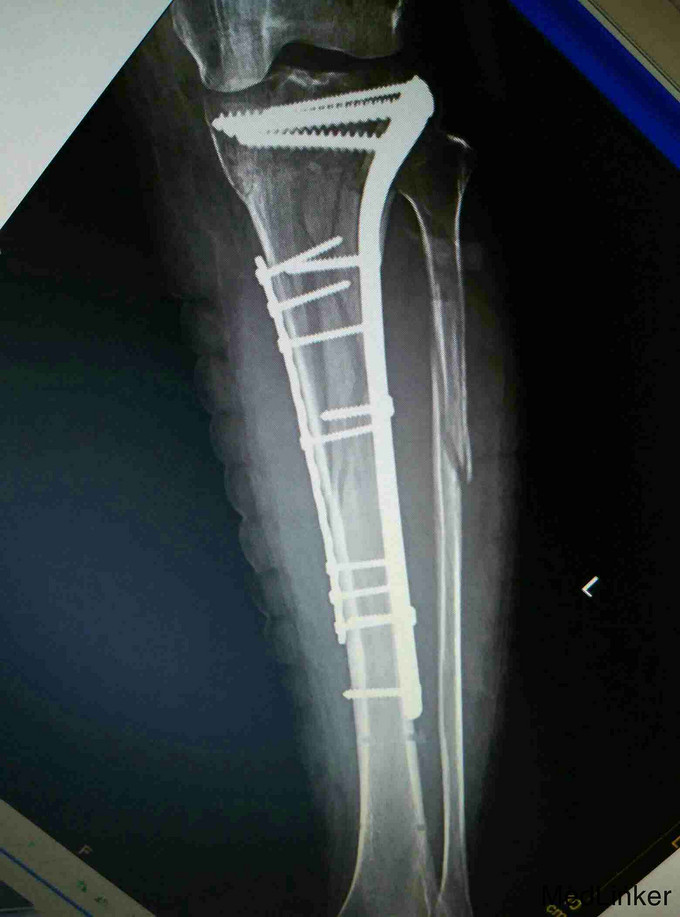

考虑为筋膜室综合征,予急诊行切开减压,考虑一期骨折复位内固定手术风险高,则行骨折端外固定架固定,同时VCD引流,待局部肿胀减轻,局部无明显张力,伤口无炎性反应后,二期行开放复位钢板固定术。

术后恢复良好,伤口正常愈合,功能佳。 讨论:小腿骨折常引起筋膜室综合征,应注意观察,特别是小腿上段骨折更容易引起筋膜室综合征,因为其血运好,出血多,如果发现筋膜室综合征或可疑筋膜室综合征,都要毫不犹豫的切开,不建议行一起的骨折端复位内固定,感染等风险较大,可暂时外固定架固定,同时VSD引流,可以减少换药及感染概率。术后7到10天局部肿胀减轻,无感染迹象后再行切开复位钢板固定术。